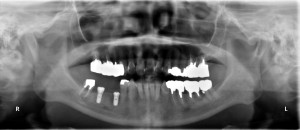

右下の567部位に2本のRN11mmを埋入しました。

5,7部にそれぞれRN11mmを埋入しました。

7番は1回法、5番部位は完全埋入としました。

術後のパノラマです。